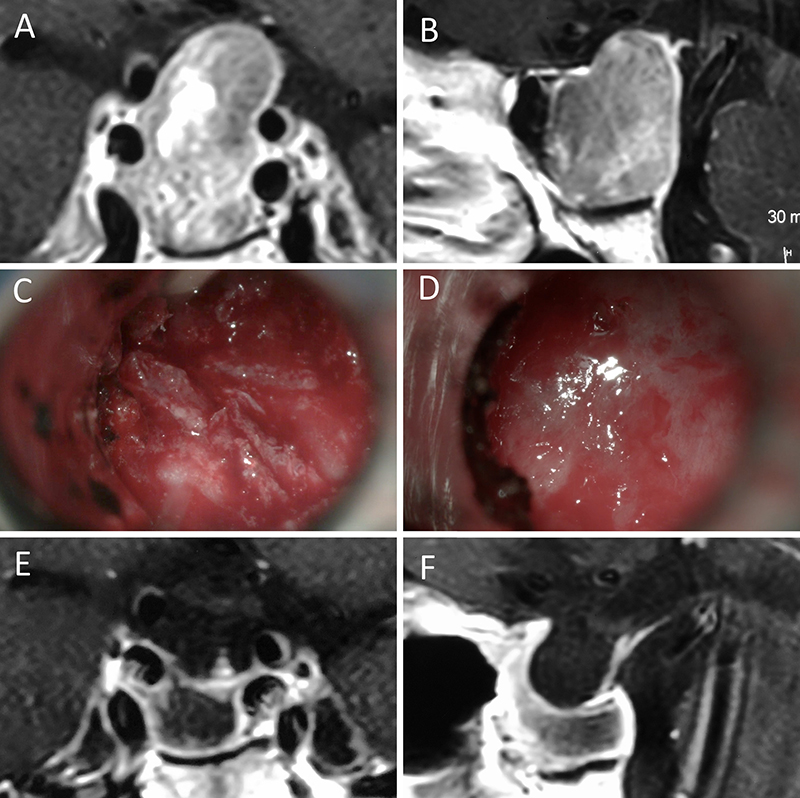

Figura 1: Macroadenoma no funcionante en mujer de 65 año s. Se decidió la cirugía tras evidenciarse crecimiento en los controles. Evolucionó favorablemente desde el punto de vista clínico-radiológico. A-B: RM preoperatoria; C-D: intraoperatorio; E-F: RM postoperatoria.

Figura 2: Macroadenoma no funcionante en mujer de 31 años. La paciente presentó en el preoperatorio déficit visual que mejoró tras la cirugía. A-B: RM preoperatoria; C-D: intraoperatorio; E-F: RM postoperatoria.